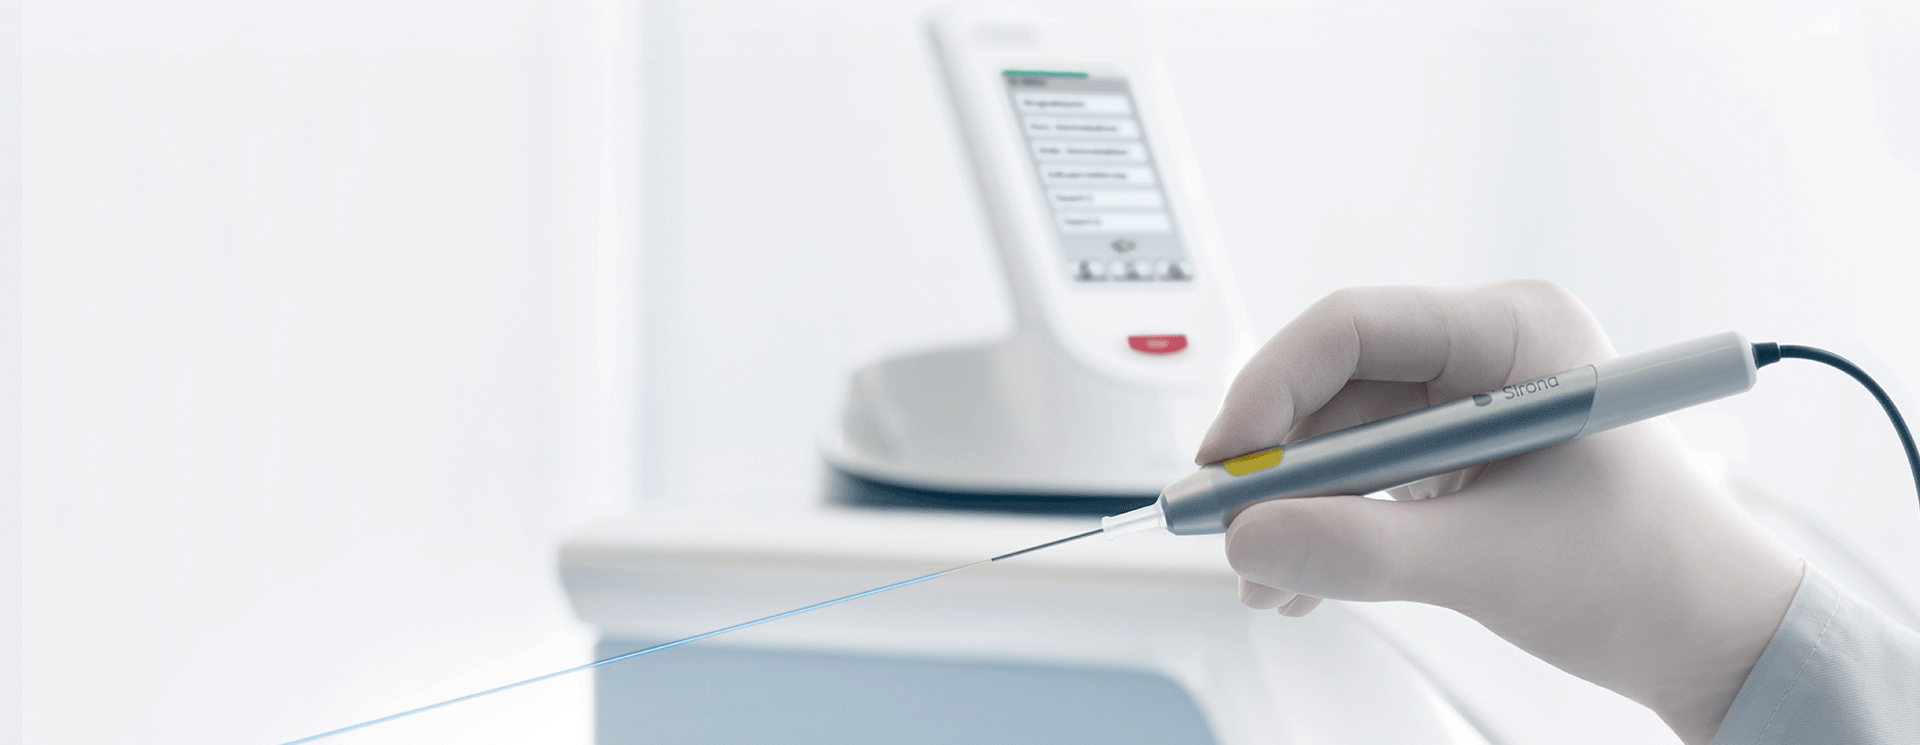

When comparing the application areas of the different laser types it becomes clear that the diode laser offers the widest range of applications.

Treatment options with the SiroLasers